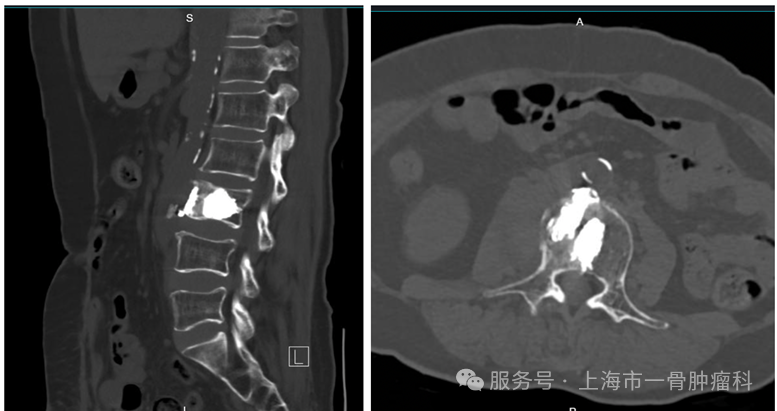

图4: L3椎体双侧OC射频消融+骨水泥成型

图5: L3椎体微创消融术后